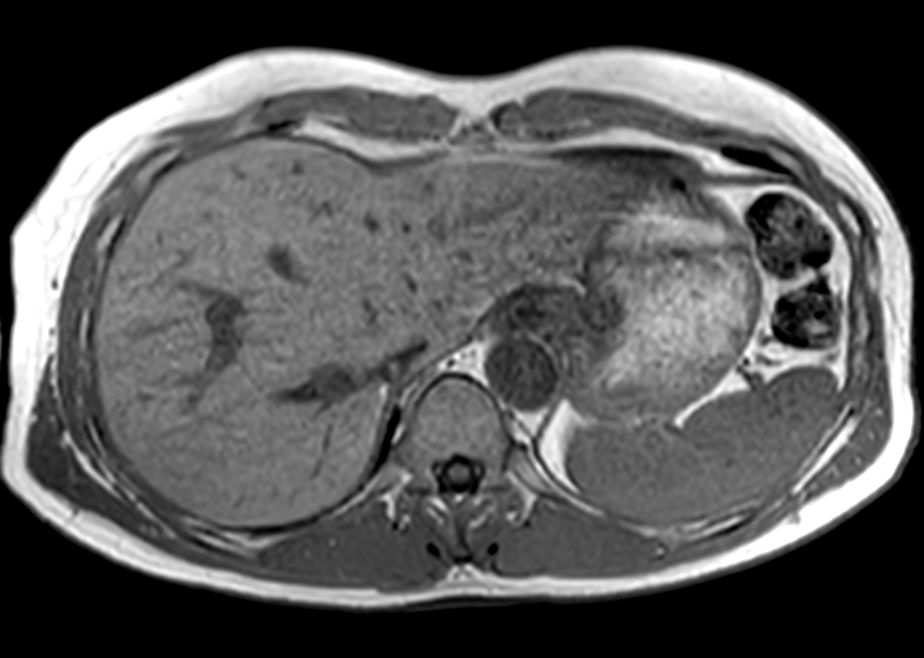

Axial Dual FFE (Out Phase)

-

Axial Diffusion (b600)